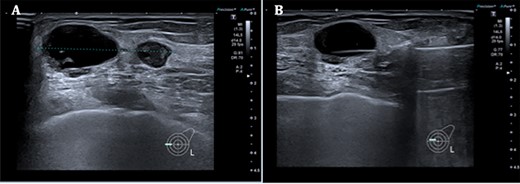

Left mammogram showing masses—A. Mediolateral oblique B. Cranial–caudal views.

Triple assessment was done—examination revealed multiple cutaneous neurofibromas in keeping her NF1. Breast examination revealed a firm irregular 2-cm lump at the 9 o’clock position of the left breast with no contralateral lumps nor any evidence of lymphadenopathy. Bilateral mammogram demonstrated a dense indeterminate mass on the left breast (Fig. 1). Targeted ultrasound scan showed two cystic-like lesions adjacent to each other (Fig. 2). A core needle biopsy was done of the larger lesion confirming grade 3 invasive ductal carcinoma—receptor status analysis revealed that the lesion was ER negative, PR negative and HER2 positive.